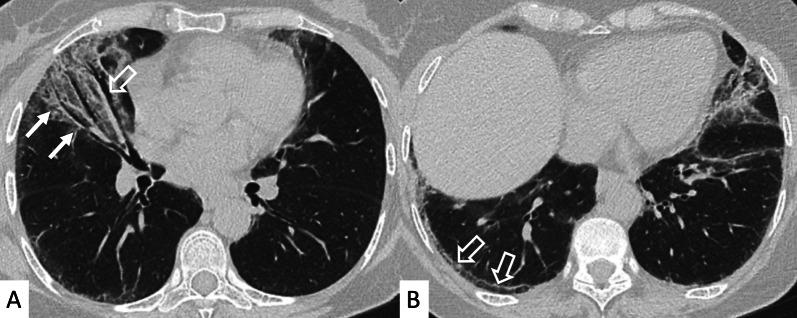

Connective tissue diseases (CTDs) include a spectrum of disorders that affect the connective tissue of the human body; they include autoimmune disorders characterized by immune-mediated chronic inflammation and the development of fibrosis. Lung involvement can be misdiagnosed, since pulmonary alterations preceded osteo-articular manifestations only in 20% of cases and they have no clear clinical findings in the early phases. All pulmonary structures may be interested: pulmonary interstitium, airways, pleura and respiratory muscles. Among these autoimmune disorders, rheumatoid arthritis (RA) is characterized by usual interstitial pneumonia (UIP), pulmonary nodules and airway disease with air-trapping, whereas non-specific interstitial pneumonia (NSIP), pulmonary hypertension and esophageal dilatation are frequently revealed in systemic sclerosis (SSc). NSIP and organizing pneumonia (OP) may be found in patients having polymyositis (PM) and dermatomyositis (DM); in some cases, perilobular consolidations and reverse halo-sign areas may be observed. Systemic lupus erythematosus (SLE) is characterized by serositis, acute lupus pneumonitis and alveolar hemorrhage. In the Sjögren syndrome (SS), the most frequent pattern encountered on HRCT images is represented by NSIP; UIP and lymphocytic interstitial pneumonia (LIP) are reported with a lower frequency. Finally, fibrotic NSIP may be the interstitial disease observed in patients having mixed connective tissue diseases (MCTD). This pictorial review therefore aims to provide clinical features and imaging findings associated with autoimmune CTDs, in order to help radiologists, pneumologists and rheumatologists in their diagnoses and management.

结缔组织病(CTDs)包括一系列影响人体结缔组织的疾病;它们包括以免疫介导的慢性炎症和纤维化发展为特征的自身免疫性疾病。肺部受累可能会被误诊,因为肺部改变仅在20%的病例中先于骨关节炎表现出现,且在早期阶段没有明确的临床发现。所有肺部结构都可能受累:肺间质、气道、胸膜和呼吸肌。在这些自身免疫性疾病中,类风湿关节炎(RA)的特征是普通型间质性肺炎(UIP)、肺结节和伴有空气潴留的气道疾病,而系统性硬化症(SSc)常表现为非特异性间质性肺炎(NSIP)、肺动脉高压和食管扩张。NSIP和机化性肺炎(OP)可见于多发性肌炎(PM)和皮肌炎(DM)患者;在某些情况下,可观察到小叶周围实变和反晕征区域。系统性红斑狼疮(SLE)的特征是浆膜炎、急性狼疮性肺炎和肺泡出血。在干燥综合征(SS)中,HRCT图像上最常见的表现是NSIP;UIP和淋巴细胞间质性肺炎(LIP)的报道频率较低。最后,纤维化NSIP可能是混合性结缔组织病(MCTD)患者中观察到的间质性疾病。因此,本图像综述旨在提供与自身免疫性CTDs相关的临床特征和影像学表现,以帮助放射科医生、呼吸科医生和风湿病科医生进行诊断和管理。